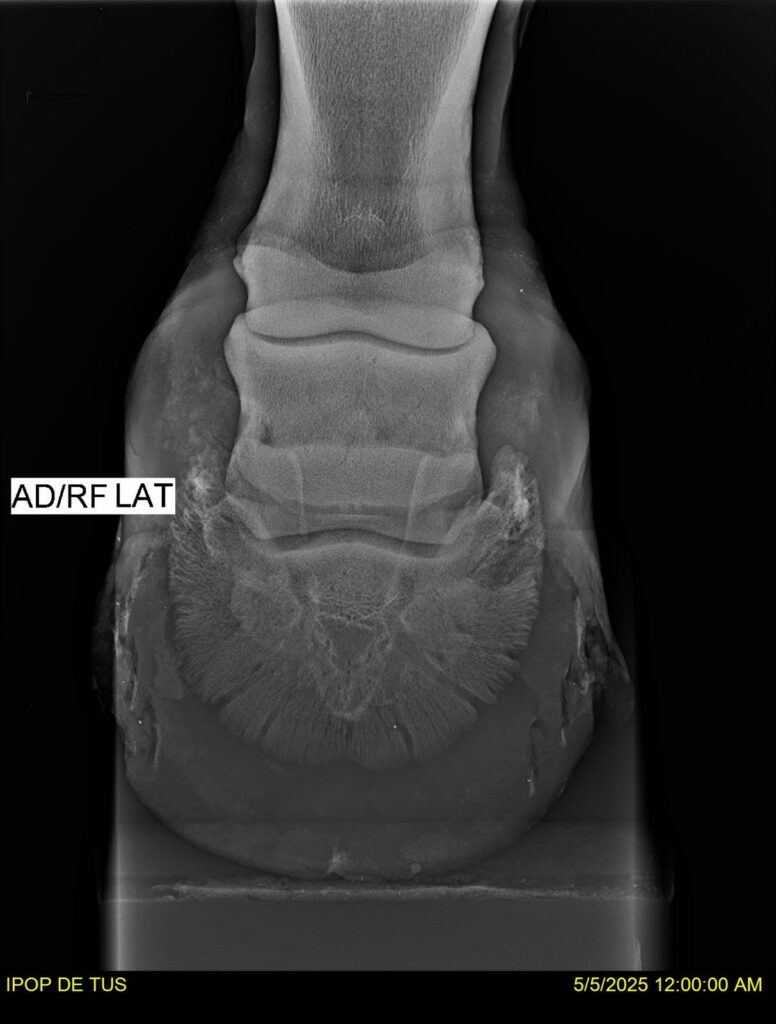

IPOP DE TUS, selle français, hongre, prendra 8 ans en 2026. LIFESTYLE x EROTICBLUS MONTOIS. Sans faute sur 125 et 130. Gentil cheval, respectueux avec des moyens et de la force. Transport OK, maréchalerie OK (pieds nus), santé RAS, Bilan clichés radios + clinique OK.

RADIOS ET CLINIQUE